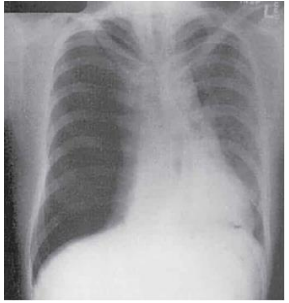

Paciente de 30 anos, masculino, tabagista e usuário de maconha,

deu entrada no Posto de Saúde com quadro de dor torácica de

início súbito (sem história de trauma recente), dispneia,

taquipneia, PA 100x70 mmHg, FC 110 bpm com ritmo sinusal.

Realizada radiografia de tórax, representada na imagem abaixo.

Assinale a opção que apresenta a principal hipótese diagnóstica para o caso.